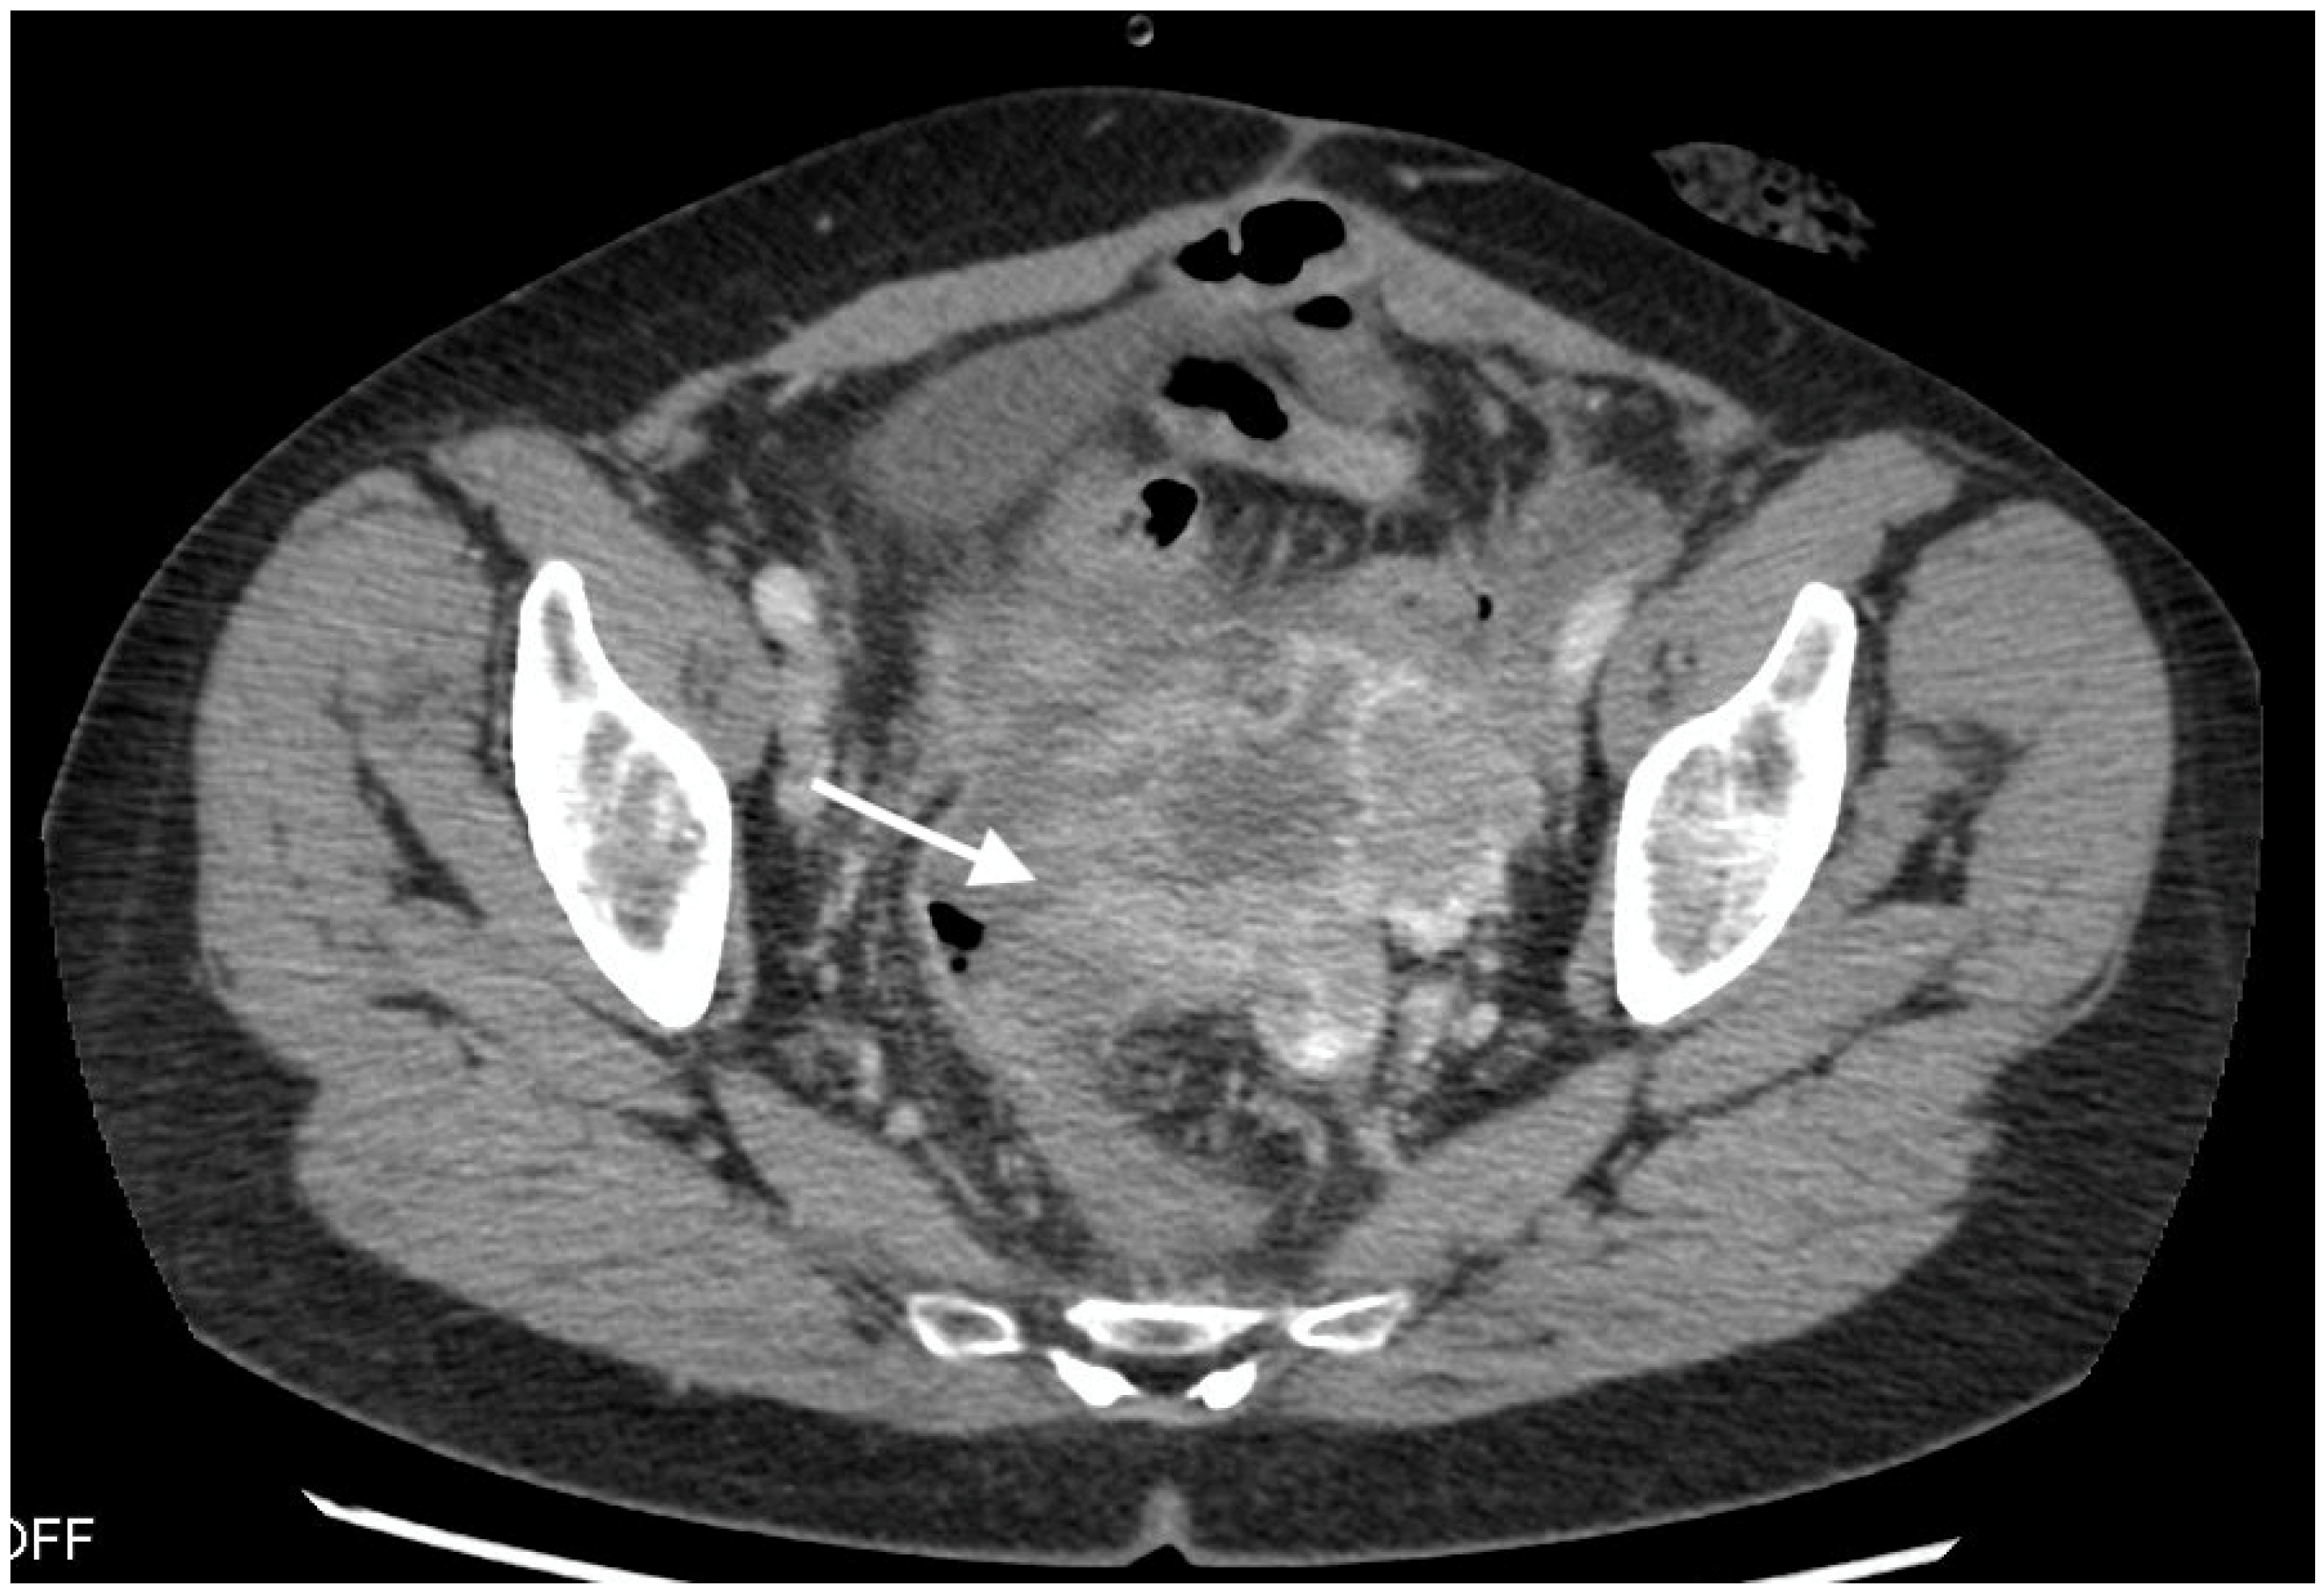

Figure 1.

Images from 58-year-old patient with carcinosarcoma of the ovary and recurrence in the rare form of giant cell carcinoma. The fistula between tumor and rectum (arrow), CT post-contrast image in venous phase obtained in the axial plane, shows pelvic tumor and adjacent intestine, fatty tissue between the tumor and intestine vanished as indirect sign of the fistula.